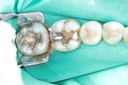

Mark Chun #29 pre-op